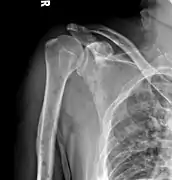

Medical imaging

The diagnostic examination of a person with suspected multiple myeloma typically includes a skeletal survey. This is a series of X-rays of the skull, axial skeleton, and proximal long bones. Myeloma activity sometimes appears as "lytic lesions" (with local disappearance of normal bone due to resorption) or as "punched-out lesions" on the skull X-ray ("raindrop skull"). Lesions may also be sclerotic, which is seen as radiodense.[70] Overall, the radiodensity of myeloma is between −30 and 120 Hounsfield units (HU).[71] Magnetic resonance imaging is more sensitive than simple X-rays in the detection of lytic lesions, and may supersede a skeletal survey, especially when vertebral disease is suspected. Occasionally, a CT scan is performed to measure the size of soft-tissue plasmacytomas. Nuclear Medicine Bone scans are typically not of any additional value in the workup of people with myeloma (no new bone formation; lytic lesions not well visualized on nuclear bone scan).

Bone pain affects almost 70% of people with multiple myeloma and is one of the most common symptoms.[2]:653[22] Myeloma bone pain usually involves the spine and ribs, and worsens with activity. Persistent, localized pain may indicate a pathological bone fracture. Involvement of the vertebrae may lead to spinal cord compression or kyphosis. Myeloma bone disease is due to the overexpression of receptor activator for nuclear factor κ B ligand (RANKL) by bone marrow stroma. RANKL activates osteoclasts, which resorb bone. The resultant bone lesions are lytic (cause breakdown) in nature, and are best seen in plain radiographs, which may show "punched-out" resorptive lesions (including the "raindrop" appearance of the skull on radiography). The breakdown of bone also leads to the release of calcium ions into the blood, leading to hypercalcemia and its associated symptoms.[23]